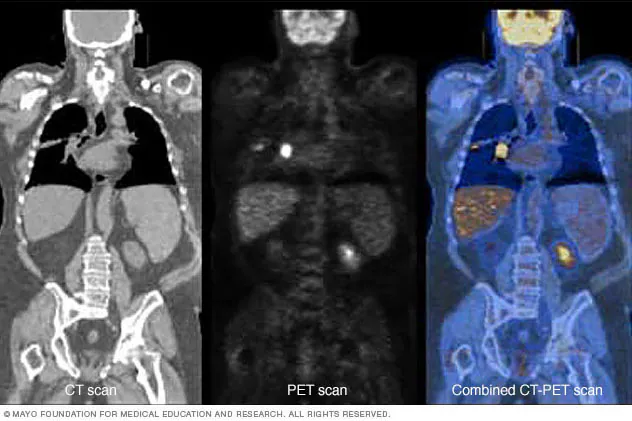

1. CT Scan (Computed Tomography)

CT scan एक widely used test है।

3. PET Scan (Positron Emission Tomography)

👉 सबसे advanced और accurate scan माना जाता है

- Cancer cells की activity detect करता है

- पूरे शरीर का scan करता है

- Early stage में भी cancer detect कर सकता है

👉 Common use: Whole body cancer detection

CT vs MRI vs PET Scan (Comparison)

- CT Scan: Fast और widely available

- MRI: Soft tissue detail के लिए best

- PET Scan: Cancer detection के लिए सबसे accurate